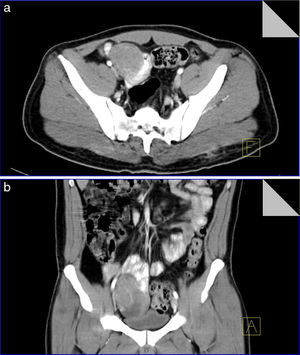

Con diagnóstico de choque hipovolémico grado ii secundario a hemorragia de tubo digestivo alto ingresa a sala de choque iniciando manejo con cristaloides y transfusión de 3 paquetes globulares, así como infusión de inhibidor de bomba de protones; a las 24h presenta mejoría clínica y sin datos de hemorragia activa, con control de hemoglobina 8.3g/dl, hematocrito 26.4% y plaquetas 125,000; se decide nueva transfusión de paquete globular y realizar panendoscopia con hallazgo de gastritis sin datos de hemorragia. Al sexto día, se presentan episodios de melena y descenso de la hemoglobina a 5.6g/dl con un hematocrito de 18.2%, por lo que se inicia transfusión de 3 paquetes globulares y preparación del colon para colonoscopia, con sospecha de probable hemorragia de tubo digestivo bajo, la cual se realiza sin evidencia de anormalidades; se solicita tomografía simple y contrastada abdominopélvica, con reporte de asa de intestino delgado con lesión tumoral de morfología ovoidea y bordes regulares adyacente a íleon que muestra realce importante durante fases contrastadas, con dimensiones de 76×48×51mm (fig. 1); el resto de las estructuras tienen características normales, concluyendo con el diagnóstico de tumor dependiente de intestino delgado.

Tomografía simple y contrastada de abdomen en corte axial y con reconstrucción coronal. a) Corte axial donde se identifica un tumor bien definido, redondo, dependiente de la pared del yeyuno, con marcada afinidad por medio de contraste, sin infiltración a tejidos adyacentes. b) Corte coronal donde se confirma dependencia del tumor a pared de asa yeyunal, condicionando moldeamiento del techo vesical sin pérdida de interfase que evidencie infiltración.